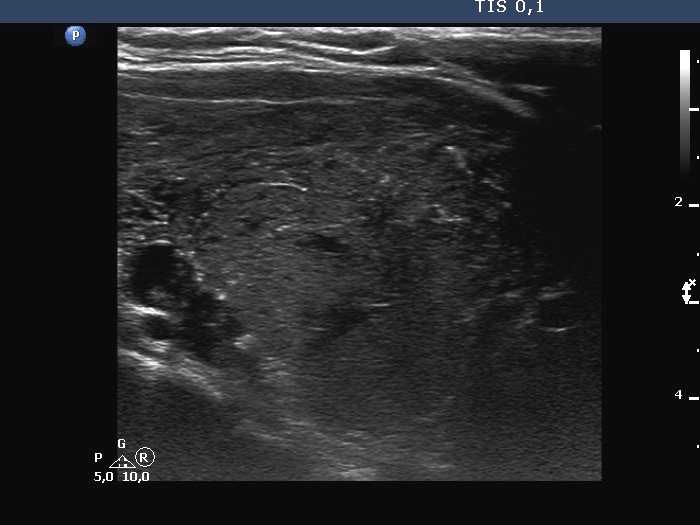

Middle-lower part of the right lobe, another longitudinal scan.